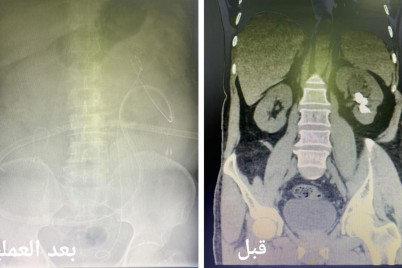

جدة - ريفان هوساوي تمكن فريق طبي متخصص بعلاج أمراض المسالك البولية من إنهاء معاناة مريض استمرت 3 سنوات بإستخراج...